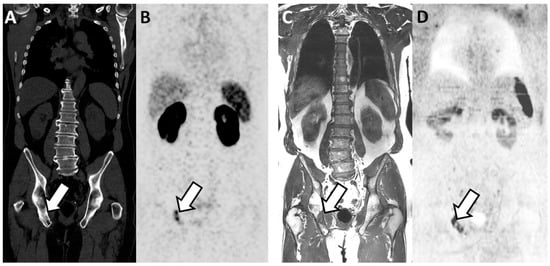

Figure 3. Discordant findings between PSMA PET/CT and WB-MRI/DWI: false negative observation of metastatic lymph node by WB-MRI/DWI in 62-year-old patient with prostate cancer at BCR (rapidly rising PSA up to 3.5 ng/mL after radical prostatectomy and pelvic irradiation). (A,B) PSMA PET/CT: reformatted coronal CT (A) and PET (B) images show unique 10 mm radiotracer-positive (SUVmax 12) left iliac lymph node considered as metastatic on the PET image (arrows in (A,B)). (C,D) WB-MRI/DWI images: corresponding reformatted high resolution T1 (C) and diffusion-weighted (D) MRI images show single left lymph node (arrows in (C,D)) that was not considered as metastatic based on its size (small diameter < 10 mm). (E) Hematoxylin and eosin stained section of resected node after robotic-assisted salvage lymphadenectomy shows the presence of a PCa metastasis with a mixed intra-ductal (*) and cribriform (**) morphology (original magnification ×300; scale bar in lower left corner).

PSMA PET-CT had higher sensitivity and specificity without reaching statistical significance (Table 5). At the patient level, the AUC for identifying metastatic patients was 0.96 (0.90–1.00) and 0.89 (0.79–0.98) for PSMA PET-CT and WB-MRI, respectively (p = 0.25). WB-MRI missed one additional patient (false negative) compared to the PSMA PET-CT. The inter-technique agreement was good (adjusted kappa = 0.74; 0.55–0.92). At the lymph node level, the AUC was 0.94 (0.87–1.00) and 0.88 (0.79–0.97) for PSMA PET-CT and WB-MRI, respectively (p = 0.34) (Figure 3). At the bone level, both modalities performed equally well with an AUC of 0.96 (0.90–100).